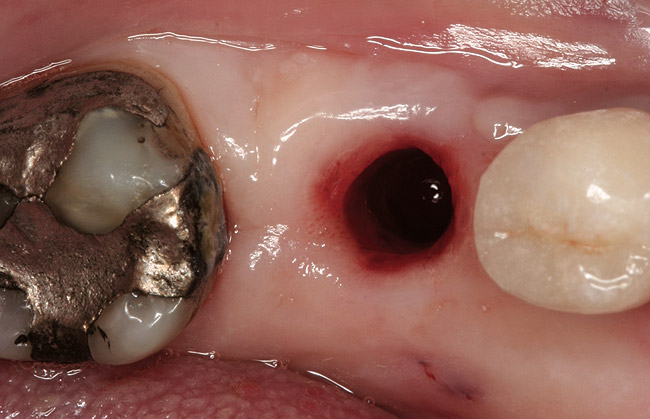

Figure 2  Following crown and abutment removal, the implant platform was exposed.

Figure 2

Figure 3  The implant was explanted by using a counter-torque ratchet.

Figure 3

Figure 4  The site following atraumatic implant removal.

Figure 4